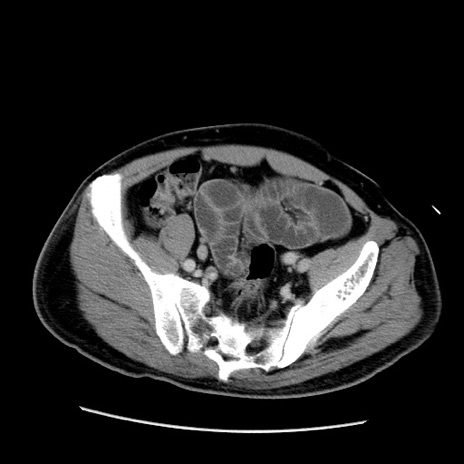

症例22(横断像)

【症例】50歳代男性

【主訴】腹痛

【現病歴】AVMからの被殻出血のため回復期リハ病棟入院中。 本日午後3時頃急に下腹部痛が出現した。

【既往歴】AVM、被殻出血、虫垂炎、高血圧

【身体所見】意識晴明、左半身不全麻痺、会話の理解は良好、36.5°C、腹部:膨隆、全体に板状硬、下腹部正中に圧痛点あり、反跳痛-、筋性防御不明、右下腹部にope scar

【データ】WBC 9400、CRP 0.06